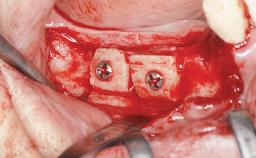

An 80-year-old female patient was referred to clinic for rehabilitation of her dentition. The patient’s medical history revealed no significant findings that would preclude routine dental and oral surgical procedures. She reported no drug allergies and was currently taking no prescription medications.

Her chief complaint was her inability to masticate efficiently due to the recent loss of her mandibular second premolars and first molars bilaterally. She expressed a desire for fixed prostheses in the shortest possible time due to her advanced age, requesting that replacement teeth should look as natural as possible. She was otherwise comfortable and not experiencing any symptoms from her teeth.

Case Type Short Space

Jaw Mandible

Area Posterior

# of Teeth 4

# of Implants 4

Guided Surgery Yes